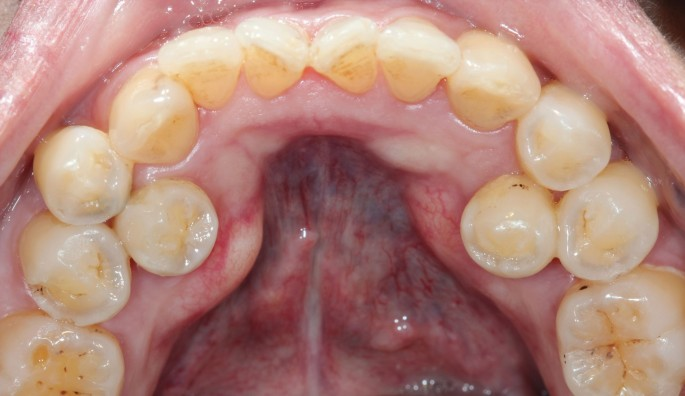

融合 or Gemination

Gemination/ Fusion

Concrescence